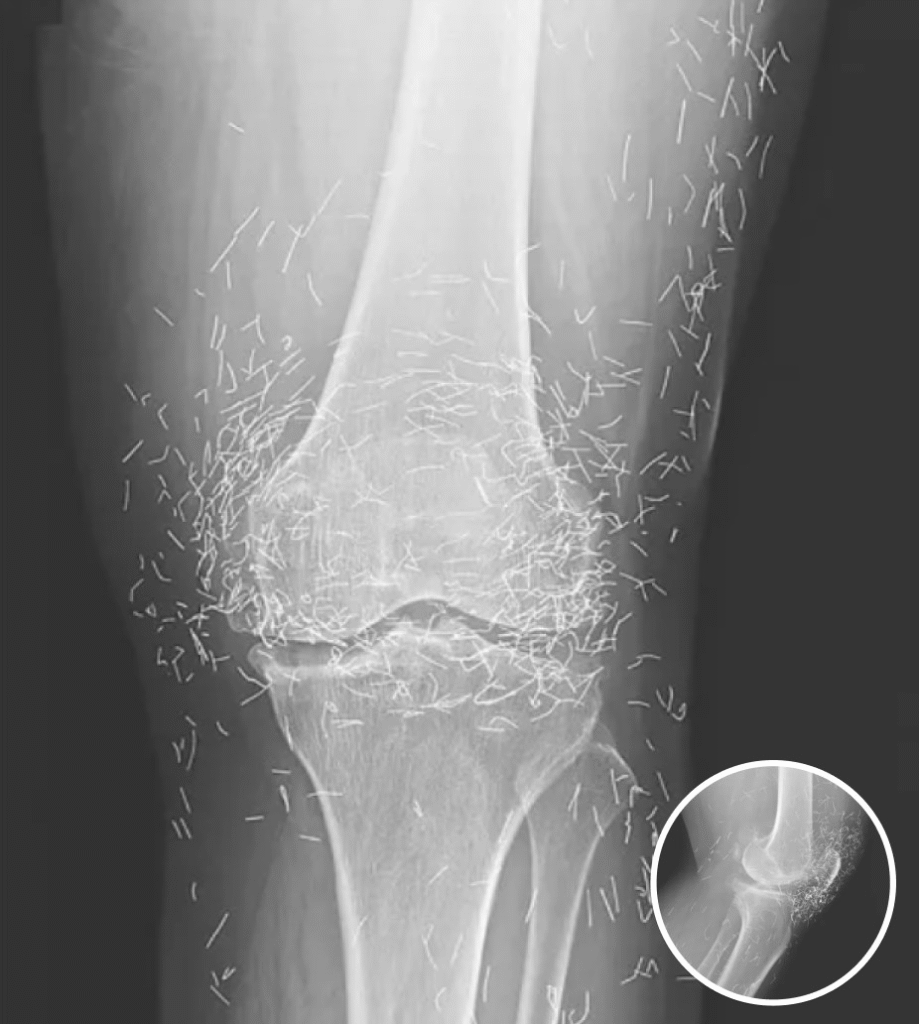

A X-ray of the patient’s knee showing acupuncture needles embedded in the tissue, Photo Credit: Reddit

A routine X-ray revealed an unexpected surprise when doctors examined the knees of a 65-year-old woman suffering from severe joint pain. What they found was nothing short of astonishing — hundreds of tiny gold needles embedded deep in her tissue.

There are other complications as well. Needles lodged in tissue can interfere with medical imaging. “They can obscure parts of the anatomy on an X-ray,” Guermazi noted. Even more alarming, patients with metal fragments in their bodies should never undergo an MRI, as the magnetic force could cause the needles to move — potentially puncturing blood vessels and causing life-threatening damage.